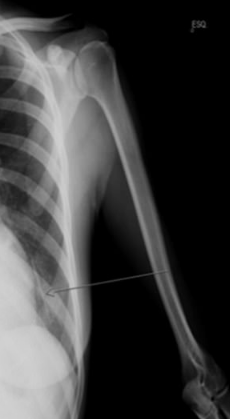

She had the implant in her body for good 8 years but since last 3 months, she had been bleeding from her vagina abnormally. On the test, the doctors were unable to spot her contraceptive device in her arm which is quite easy to spot.

It is a hard long stick in the upper side of the arm but it was not there in her’s. After a scan of her body, the rod was found out to be in her lungs.

The doctors said that it is important to place the device right. The implant was rooted so deeply in her body that it went away with blood and reached the lung.